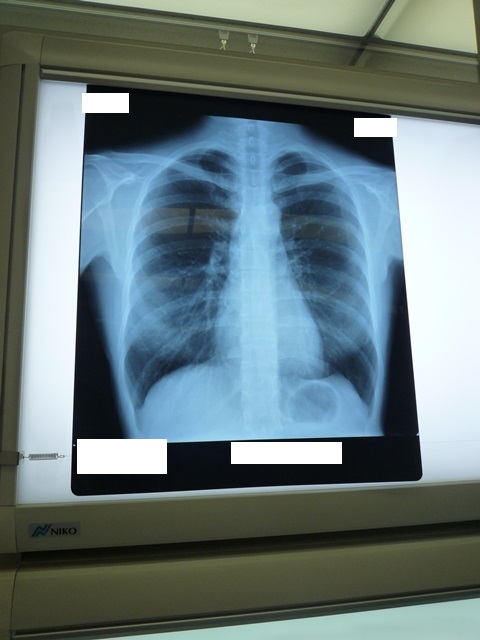

「……今、したほうがいいのは、レントゲン。今から行こうか」

「肺に何かあるにしても、心臓に何かある場合でも、今、考えられる範囲やったら、レントゲンで変な映り方をすると思うねん。逆になければ、緊急の何かということはないと思う」

レントゲンを撮ってもらう。酸素の濃度も計ってもらうと、99%あった。

「心配ないね。キレイやわ」

「ありがとうございます。良かった! あの、レントゲンの写真を撮っていいですか?」

「はい、どうぞ! (撮りやすい位置にフィルムを動かしてくださる)」

「だから、何してもいいよ」